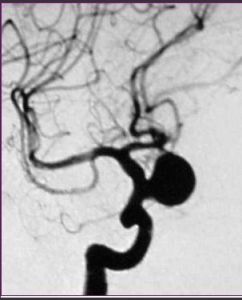

3.腦血管造影是確診顱內動脈瘤必須的檢查方法,對判明動脈瘤的準確位置、形態、內徑、數目、血管痙攣和確定手術方案都十分重要。DSA更為清晰。,經股動脈插管全腦血管造影,可避免遺漏多發動脈瘤。病情在三級以下,腦血管造影應及早進行,三級和三級以上病人可待病情穩定後,再行造影檢查。及早造影明確診斷,儘快手術夾閉動脈瘤,可以防止動脈瘤再次破裂出血。首次造影陰性,可能因腦血管痙攣而動脈瘤未顯影,高度懷疑動脈瘤者,應在3個月後重複造影。

顱內動脈瘤2.因顱內動脈瘤多位於顱底部WiLLis動脈環,直徑小於1.0C的動脈瘤,CT不易查出。直徑大於1.0cm,注射對比劑後,CT掃描可檢出。MRI憂於CT,動脈瘤內可見流空。MRA可提示不同部位動脈瘤,常用於顱內動脈瘤篩選。三維CT(3D—CT)從不同角度了解動脈瘤與載瘤動脈的關係,為手術夾閉動脈瘤決策提供更多的資料。